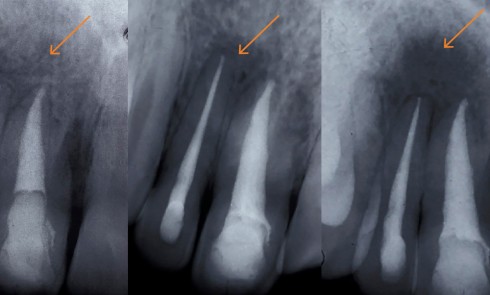

Article réservé à nos abonnés Les techniques de revascularisation endodontique peuvent-elles réellement renforcer les dents ?

La nécrose pulpaire des dents permanentes immatures constitue encore aujourd’hui pour le praticien une situation clinique complexe. En effet, la...